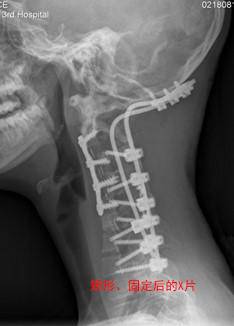

正常颈椎是稍微向前方弯曲的,这是为了直立行走。但是,这个孩子的颈椎严重向后弯曲,这在医学上叫做严重的颈椎后凸畸形。

其次,这个手术的关键除了矫正畸形的弯曲,还要给颈椎打上固定架子,用外力辅助,这样才不会复发。

在多个学科的共同参与下,这个孩子终于完成了手术。

这个孩子前后经历了大大小小4次手术,最后顺利出院了。